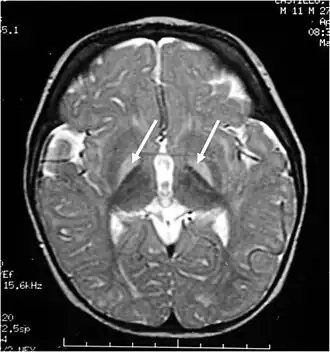

Imagerie par résonance magnétique cérébrale. Les ganglions de la base, hyperintenses en pondération T2, sont marqués d'une flèche blanche.

L'ictère nucléaire désigne le stade avancé de l'atteinte cérébrale chez le nouveau-né secondaire à l'accumulation de bilirubine (ictère).

La bilirubine libre, c'est-à-dire non conjuguée, si elle est trop élevée (au-delà de 250 à 300 µmol/L (environ 14,5 à 17,5 mg/dL) chez l'enfant à terme) se fixe sur les noyaux gris centraux entraînant des lésions cérébrales et une atteinte des nerfs crâniens (le VIII en particulier) irréversibles à ce stade. Cette augmentation de la bilirubine est liée à une hyper-hémolyse d'une part, et/ou au retard (prématurité) ou à l'absence de la mise en route des enzymes hépatiques nécessaires à la glycuroconjugaison de la bilirubine. Cette glycuroconjugaison était inutile in utero, la bilirubine étant éliminée par voie placentaire.

Outre l'ictère, ce sont les symptômes neurologiques qui sont au premier plan, avec un risque de séquelles : syndrome extrapyramidal, mouvements de type chorée-athétose, parésie oculomotrice et surdité.